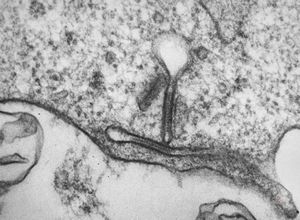

F,68y. | collagenous and elastin fibers from corium